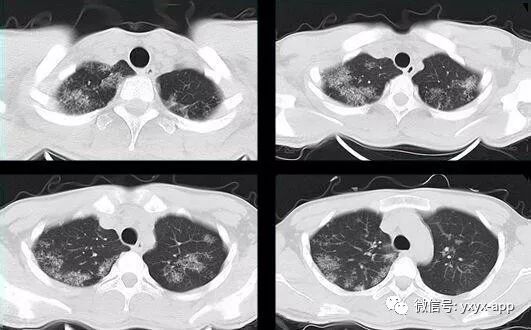

评论:两肺斑片状磨玻璃影,与周围组织分界清楚,呈“地图样”表现,部分病变延伸至胸膜下,部分小叶间隔增厚,气管居中,肺门及纵膈未见肿大淋巴结影,未见胸腔积液。患者青年男性,临床症状轻微影像表现严重,抗炎治疗无效。考虑肺泡蛋白沉积症

【结果】肺泡灌洗病理证实:肺泡蛋白沉积症

1、两肺较淡的斑片状磨玻璃影,不呈叶段分布,病变可延伸至胸膜下,其中磨玻璃影中可见小结节影,磨玻璃影与正常肺组织分界清楚,形成“地图样”改变,这种地图样分布的原因,可能是由于这种斑片影以肺小叶为病变单位,小叶间隔在一定程度上限制了病变的蔓延;

2、由于小叶间隔和小叶内间隔的增厚形成网格状阴影改变,弥漫的磨玻璃影及其内部的网格小叶间隔增厚形成了“铺路石样”改变;

3、实变区具有多样性,多种不同程度的病变共存,病灶内可见支气管气像;

4、病变部位以肺门及双下肺明显。